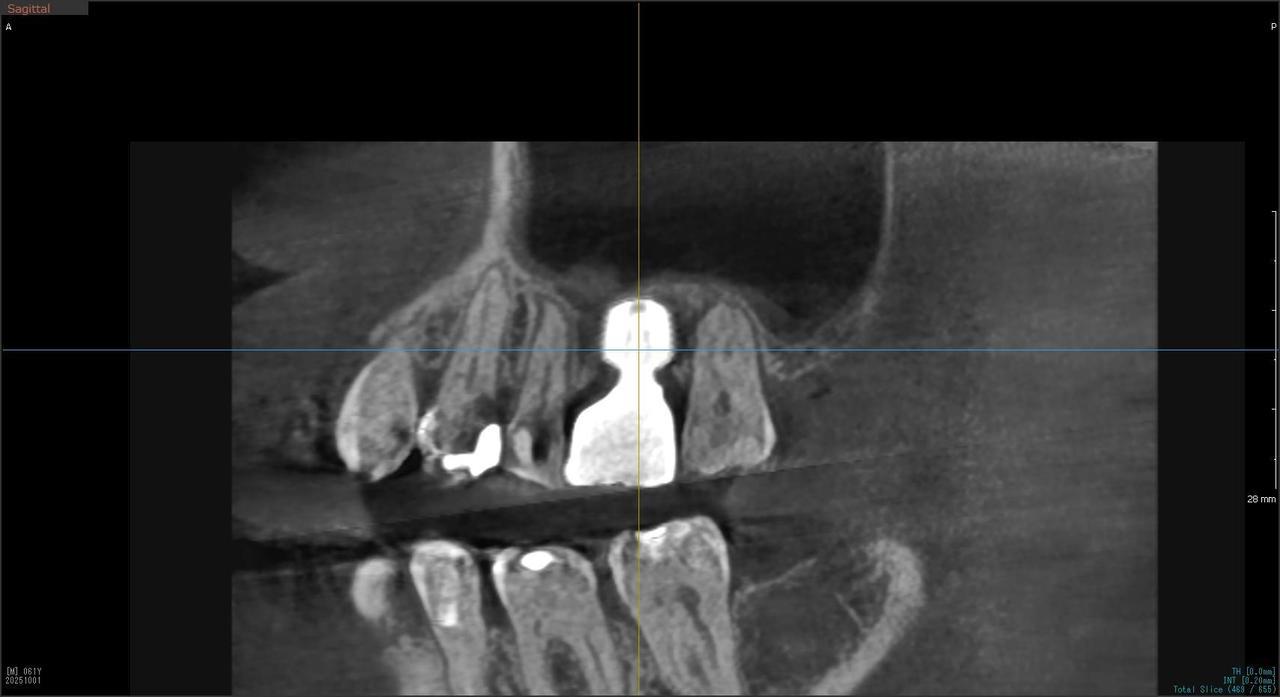

3.左上5の頬・舌側の大幅な骨欠損と上顎既存骨3mmまでの骨欠損がおこった症例に対しておこなったインプラント治療

Before

枚方市のインプラントの症例

I・K 様 女性 40代

症状としては、左上5の歯根破折を起こしていたため、排膿と自発痛をみとめた。それにともなう骨の大きな欠損。

治療法としては、炎症が強くたったためと、炎症による頬側側歯肉の退縮を認めていたために、まず、抜歯を行い上顎洞内及び歯抜した周囲組織の回復を試みた。その後、患者様がインプラント治療を希望したため、薄い上顎骨に対しては、グラフトレスサイナスリフト、骨欠損部には、人口骨補填を行い、頬側歯肉が退縮していることを改善するために、1回法でリーリングアバットメントを装着して、アバットメントの上に歯肉が覆うようにして、歯肉のボリューム回復を行った。2か月後、インプラントが骨と結合していることを確認して、光学印象を行い、2週間後にアバットメントとジルコニアクラウンを装着した。

治療結果としては、大幅な骨欠損があったが、グラフトレスサイナスリフトと骨欠損部に人工骨を補填して、抜歯した穴が自然に治る状態にしたことで、2か月半という短い期間での治療を完了することができた。(仮に、GBRや通常のサイナスリフトでの治療を行っていたら、最低でも1年は、かかってくる治療であると考える。)また、今回は、即時荷重を避け、1回法での治療を行ったことで、噛めない期間ができてしまったが、1回法で行ったことにより、歯肉のボリュームが増して、ブラッシングがしやすい口腔内環境にすることができた。低侵襲で、短時間で、治療を終えることができ、また、審美性・機能性の回復も行えたことができた。

治療の期間・回数:約2.5か月、6回

治療の価格:368,500円(税込)

治療費の内訳:インプラント基本料(フィックスチャー及び手術費用、投薬費用、レントゲン費用、インプラント上部費用(アバットメントおよびジルコニアクラウンの費用用)330000円(税込み)。オプション費用グラフトレスサイナスリフト費用プラス人工骨費用 38500円(税込み

治療のリスクや副作用:手術後に、痛みや腫れ、出血、合併症などを引き起こす可能性があります。噛む感覚がご自身の歯と異なる場合があります。見た目がご自身の歯と異なる場合があります。手術後にメインテナンスを継続しないと、インプラントが抜け落ちる可能性があります。